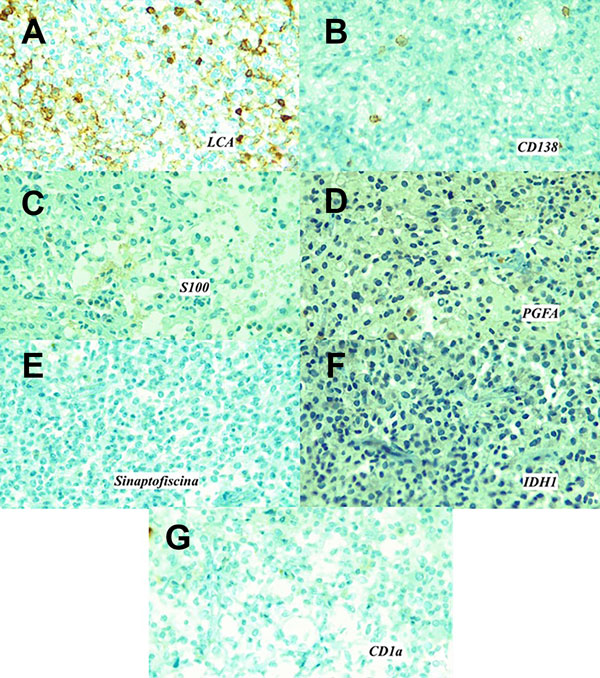

Inmunohistoquímica: reveló positividad para LCA +++/+++ en membrana de linfocitos acompañantes, positividad también para CD138 +++/+++, así como positividad para CD68 +++/+++ confirmando estirpe histiocitaria. En contraste, se demostró negatividad para S100, PGFA, sinaptofisina, citoqueratina, CD1a, IDH-1 y BRAF-V600E (Figura 4).

Figura 4. A) Antígeno leucocitario común (LCA / CD45). Población linfoide positiva. B) CD138 (sindecano-1) positivo. Inmunohistoquímica negativa para C) Proteína S100. D) Proteína gliofibrilar ácida (PGFA) (marcador de diferenciación glial). E) Sinaptofisina, (asociada a la vesícula presináptica). F) IDH-1 (isocitrato deshidrogenasa), no presenta mutación. G) CD1a.

La inmunohistoquímica en la mayoría de estos pacientes demuestra positividad para CD68, vimentina, VIIIa, HAM56 y LYS; así como negatividad a CD1a y S100.2 En el caso expuesto, se presenta con inmunohistoquímica positiva solo para LCA, el cual es un antígeno de expresión para población linfoide, así como el CD138 y el CD68, los que tienen relación con células plasmáticas y marcador de histiocitos, respectivamente.